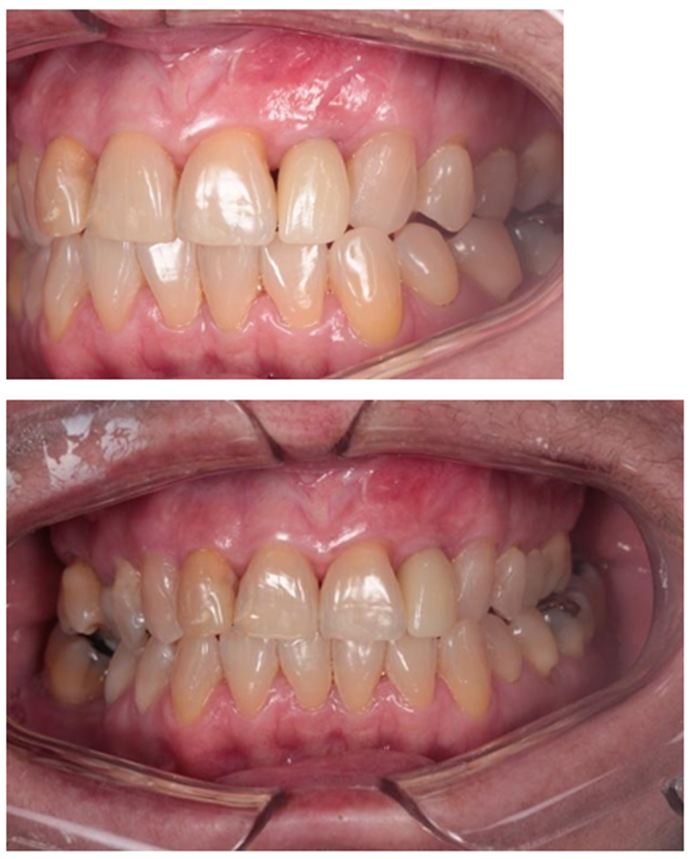

A escolha da técnica empregada justifica-se pela menor morbidade do procedimento cirúrgico e melhor acurácia no posicionamento do implante; conforme demonstrado por Nomiyama et al., 2022, ao utilizar o Sistema Implacil de instalação de implantes pela técnica guiada por computador. Imediatamente após a colocação do implante, foi instalada prótese provisória sem contato oclusal sobre pilar Ideale 3.3 x 4. Depois de quatro meses de pós-operatório, foi feito o escaneamento do componente protético utilizando transferente digital Exocad e a prótese em zircônia foi finalizada (Figuras 4 e 5).

Portanto, ao se comparar o resultado obtido ao final do tratamento da paciente com a condição inicial (Figura 6), podemos sugerir que este tipo de abordagem terapêutica é capaz de devolver estética e função mastigatória para este perfil de condição clínica tão desafiadora.